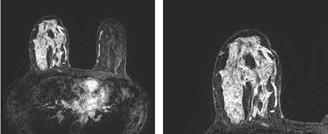

Un alt algoritm este dedicat IRMului cerebral, unde realizează volumetria structurilor encefalice și evidențiază leziuni demielinizante, aspecte esențiale pentru diagnosticul și monitorizarea bolilor neurodegenerative, precum scleroza multiplă. <figurile 2, 3, 4, 5> Un avantaj major îl constituie posibilitatea de a efectua comparații longitudinale între examene succesive, facilitând evaluarea dinamică a progresiei bolii sau a răspunsului la tratament, prin cuantificarea modificărilor de volum sau a numărului de leziuni. De asemenea, utilizăm instrumente de IA dedicate angio-IRM, capabile să identifice automat anevrismele cerebrale și să ofere informații privind dimensiunea, localizarea acestora și urmărirea în timp a acestor leziuni vasculare, oferind medicului posibilitatea de a aprecia evoluția și de a decide conduita optimă. <figura 6> În domeniul imagisticii prostatei, un